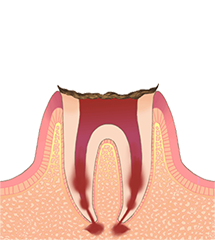

C3重度う蝕

エナメル質、象牙質を貫通し、歯髄(歯の中にある神経や血管)まで到達した虫歯です。急性症状がある場合は、鼓動に連動したような痛み(拍動痛)が現れ、特に夜になると眠れないほどの痛みが出ることがあります。すぐに根管治療が必要です。